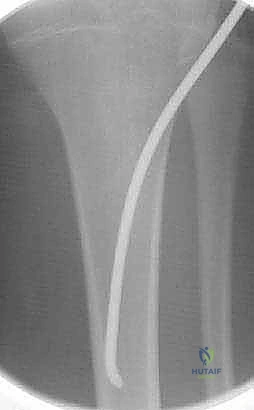

- المسامير النخاعية المرنة (Flexible Intramedullary Nails - TENs): وهي تقنية حديثة ومثالية للأطفال. يتم إدخال مسامير مرنة من التيتانيوم داخل تجويف العظم عبر شقوق صغيرة جداً (Minimally Invasive). تعمل هذه المسامير كدعامة داخلية تسمح للعظم بالالتئام بسرعة دون فتح جراحي كبير، وتوفر ثباتاً ممتازاً.

- استخدام جهاز الأشعة القوسي (C-Arm Fluoroscopy): يُستخدم هذا الجهاز المتطور طوال العملية لتوفير صور أشعة حية ومباشرة، مما يسمح للدكتور هطيف برؤية العظم من الداخل دون الحاجة لشقوق جراحية كبيرة.

- تقنية التدخل المحدود (Minimally Invasive): في حالة استخدام المسامير المرنة (TENs)، يتم عمل شقين صغيرين (حوالي 1-2 سم) بالقرب من الركبة أو الكاحل.

- تمرير المسامير والتثبيت: يتم إدخال المسامير المرنة بمهارة فائقة داخل تجويف العظم وتوجيهها لتتجاوز منطقة الكسر، مما يعيد العظم إلى استقامته الطبيعية ويثبته بقوة.